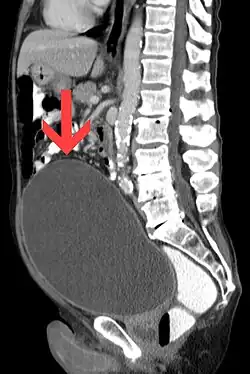

Liegt eine chronische Harnverhaltung vor, staut sich der Urin oft bis in die Nieren zurück und führt dort zu druckbedingten Schädigungen. Dabei treten als typische Befunde Hydroureter, Hydronephrose und eine Erhöhung der harnpflichtigen Substanzen auf. Therapeutisch erfolgt zunächst die Ableitung mit Harnröhrenkatheter oder suprapubischem Katheter. Bei bestehender Druckschädigung der tubulären Nierenfunktion kommt es nach der Entlastung häufig zu einer polyurischen Phase mit einer Urinausscheidung von bis zu 6 Litern am Tag.